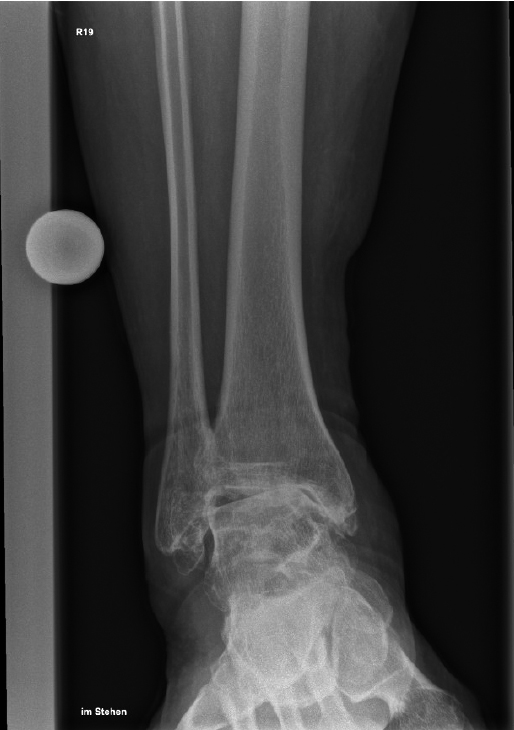

Da die klinischen Phänotypen der Sichelzellkrankheit variieren, sind die Indikationen für eine HSZT bei Patientinnen und Patienten mit Sichelzellkrankheit, im Gegensatz zu jenen mit Thalassämie, nicht universell definiert. Eine der allgemein akzeptierten Indikationen für HSZT bei Sichelzellkrankheit ist die Erkrankung des zentralen Nervensystems – verbunden mit dem Risiko wiederkehrender oder fortschreitender zerebraler Infarkte – trotz angemessener Transfusionstherapie. Andere schwere Komplikationen wie Osteonekrosen, pulmonale Hypertonie, Sichelzellnephropathie, rezidivierende venöse okklusive Krisen, akutes Thoraxsyndrom und Milzsequestrationskrise können ebenfalls als Indikationen für HSZT in Betracht gezogen werden, da sie mit einer erheblichen Morbidität und Beeinträchtigung der Lebensqualität einhergehen.